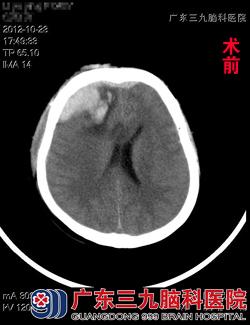

据了解,黎女士于2012年10月22日下午18时不幸发生车祸,当即出现不省人事,合并头部、口腔、鼻腔出血,呼叫无反应,被120急送当地医院救治,当地医院CT检查示:额骨粉碎性开放性骨折,右额叶挫裂伤并血肿形成,胸部DR示:创伤性湿肺;予以额部伤口填塞、压迫包扎止血,双侧鼻腔填塞纱条止血,气管插管保持呼吸道通畅,予以脱水、止血、补液等处理,治疗后黎女士病情无明显好转,意识状态进一步加重,为求进一步治疗而来到广东三九脑科医院。www.999brain.com

入院查体见黎女士呈深昏迷状态,可以自主呼吸,但呼吸稍深而快,颈软,双肺呼吸音粗,可闻及湿性罗音,四肢对刺痛无明显反应。头颅CT示:右侧额叶挫裂伤并血肿形成,前额跨中线硬膜外血肿,颅骨粉碎性骨折。完善术前检查,跟家属交待病情后,急诊在全麻下行冠切入路颅内血肿清除+双侧额颞顶去骨瓣减压术+气管切开术。术程顺利,术后回ICU继续治疗。术后5周,黎女士得以康复出院,出院时意识康复良好,四肢活动自如,可自行行走。www.999brain.com